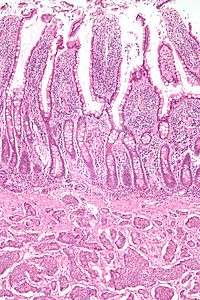

| Picture of a carcinoid tumour that encroaches into lumen of the small bowel. Pathology specimen. The prominent folds are plicae circulares, a characteristic of small bowel. | |